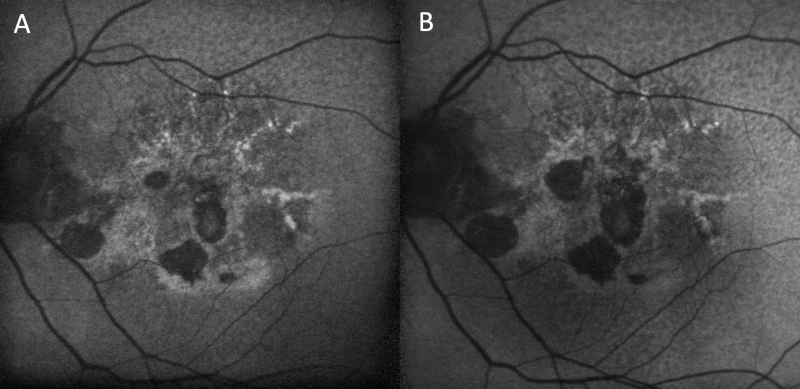

Progression of dry age-related macular degeneration on blue lightshort-wavelength fundus autofluorescence (Spectralis). (A) Left fundus of a patient with geographic atrophy showing hypo-AF patches representing areas of geographic atrophy surrounded by hyper-AF representing areas with sick retinal pigment epithelium. (B) Progression of geographic atrophy represented by expanding areas of hypo-AF.